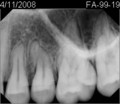

• C48EF658-5A17-4EFC-98B6-6DA55FE0F887.jpeg

C48EF658-5A17-4EFC-98B6-6DA55FE0F887.jpeg

15 KB · Views: 4